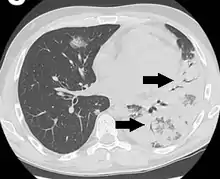

An air bronchogram is defined as a pattern of air-filled bronchi on a background of airless lung.[1]

In pulmonary consolidations and infiltrates, air bronchograms are most commonly caused by pneumonia or pulmonary edema (especially with alveolar edema).[2][3]